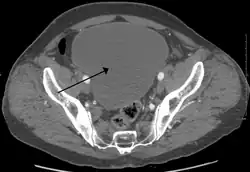

| Urinary retention with greatly enlarged bladder as seen by CT scan. | |

As seen on axial CT -